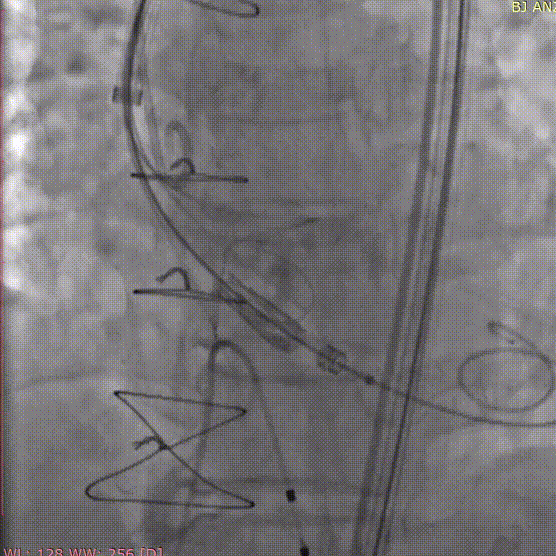

新一代经血管介入生物主动脉瓣系统

拥有全球知识产权的杰成医疗瓣膜产品,获得国内外专家的高度认可。除已上市的J-Valve经心尖介入生物主动脉瓣置换系统以外,新一代经血管系统已在各大心血管中心逐步开展临床研究。

J-Valve经心尖介入生物主动脉瓣置换系统是全球首款获官方批准可有效治疗主动脉瓣关闭不全(反流)和狭窄双适应症的TAVR系统。该系统具有自主定位装置,在国内首次提出并应用原生辦叶配合短支架设计,大幅度降低辦周漏及Ⅲ°传导阻滞发生率,起搏器植入率的五年临床随访结果仅7.4%。它是我国经首个批量逆向输出欧美地区的高端医疗器械产品。

此次周玉杰教授、张海波教授团队手术应用的杰成经血管介入瓣膜,在延续了上一代J-Valve系统优势的基础上,采用经股动脉(经血管)入路,为患者提供了更多的入路选择,同时具有手术时间更短,手术创伤更小,病人恢复更快等优点,将给更多的主动脉瓣狭窄及重度反流患者带来福音。